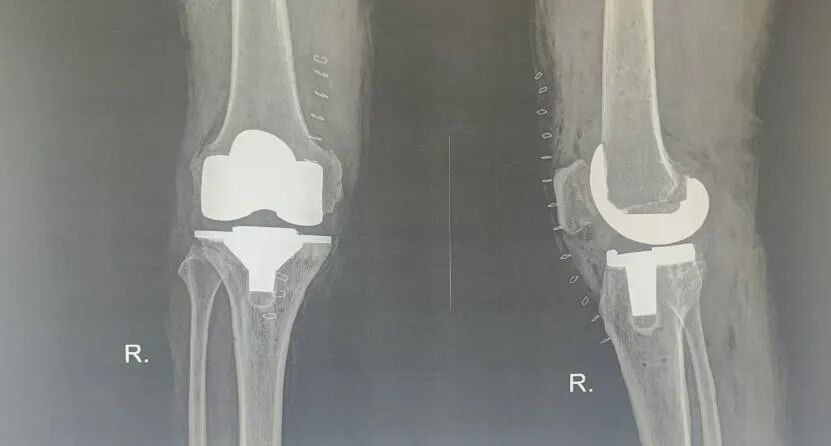

首台机器人辅助全膝关节置换手术

患者裴某,男性,66岁,患双膝关节疼痛长达20年之久,症状在行走及体力活动后显著加剧,慕名前往佳木斯骨科医院关节外科王忠春教授门诊就诊。经诊断,确诊为“双侧膝关节骨性关节炎”,鉴于其病程漫长并伴有一定程度的关节畸形,加之骨质状况不佳,王忠春教授及其团队决定采用机器人辅助手术技术进行辅助手术。

医疗团队充分利用了机器人的智能手术规划系统,根据患者的个体特征进行了精准的手术规划,并利用ARTHROBOT可视化、数字化和精准化的优势,通过实时导航系统辅助定位,仅用20分钟完成膝关节精准截骨和假体安装,假体安装位置与规划完全一致,完全实现了功能力学定线,并实现了内外侧和伸屈间隙完全平衡,手术全程出血量少,软组织干扰小,操作时间较传统手术明显缩短。

术后次日,患者在助行器辅助下顺利下床活动,其膝关节疼痛症状得到明显缓解。裴先生感慨:“现在膝盖不疼了,走路也稳了,终于能回归正常生活!”。王忠春教授表示,机器人辅助手术能够为患者提供定制化的手术规划,实现功能力学定线,术中可根据患者的软组织平衡情况调整截骨量和截骨角度,减少对软组织松解的需要。此技术不仅提升了手术精准度,还有效降低了术后感染、假体松动等并发症的风险,加速了术后康复进程,为复杂膝关节疾病患者提供了更优解决方案。